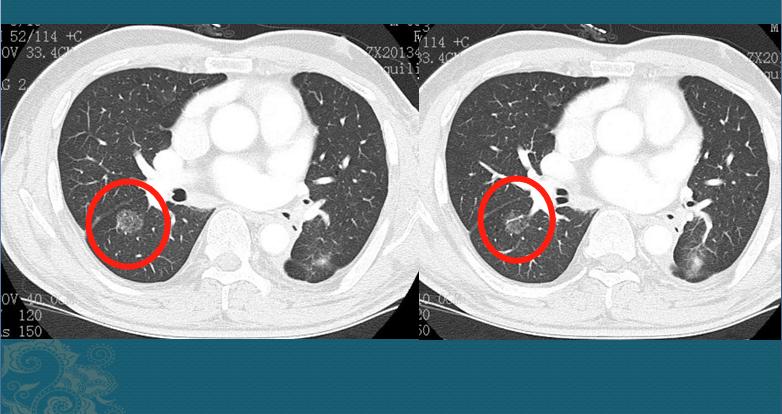

有个知识点要注意,纯磨玻璃结节如果>3.0cm,不属于微浸润,要归类于浸润性腺癌,分期为T1a。如下图:

本图片来自山东肿瘤医院黄勇教授

这是一位49岁男子,体检发现右肺纯磨玻璃结节,边界清晰,形态不规则,最大径3.9cm,浸润性腺癌,影像分期属于T1a。